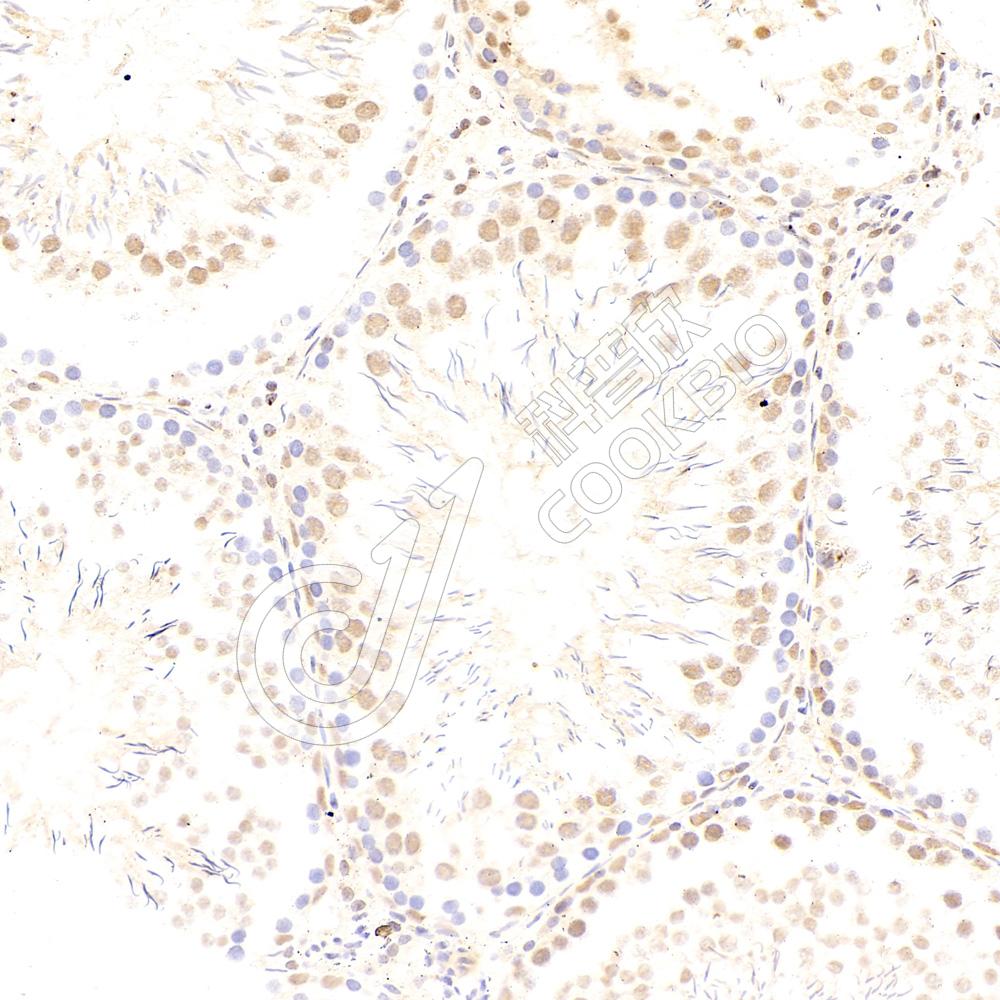

IHC检测MyD88蛋白(货号 K133807).

样品: 小鼠lps(24h)诱导肾脏炎症模型, 4%多聚甲醛 (货号KSG1101) 固定12-24小时.

抗原修复: 柠檬酸抗原修复液(干粉, pH 6.0) (KSG1201), 98℃, 20分钟.

—抗: 1: 300稀释, 4℃ 孵育过夜.

二抗: S-vision免疫组化多聚二抗(山羊抗兔),即用型 (货号KB3906), 室温孵育20分钟.

样品: 大鼠lps(24h)肺诱导炎症模型, 4%多聚甲醛 (货号KSG1101) 固定12-24小时.